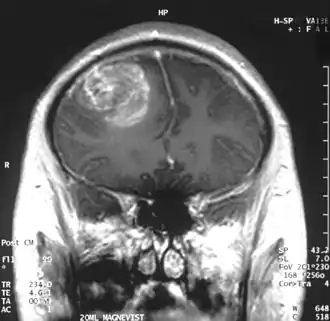

.jpg)

Quando visto através da ressonância magnética, os glioblastomas frequentemente aparecem como lesões com realce em anel. No entanto, esta aparência não é específica, já que outras lesões como abscessos, metástases e esclerose múltipla tumefativa podem ter uma aparência similar.[12]

O diagnóstico definitivo do glioblastoma multiforme requer uma biópsia estereotática ou uma craniotomia com ressecção do tumor e confirmação patológica.